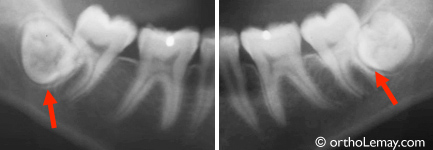

Bien que les deux dents de sagesse inférieures de cette femme de 24 ans soient partiellement sorties en bouche, elles sont recouvertes de gencive (semi-incluses) et difficiles à nettoyer. Elles sont devenues cariées en quelques mois seulement (flèches et zones sombres sur les radiographies indiquent la carie). Il est préférable de faire extraire ces troisièmes molaires avant que le problème s’aggrave.